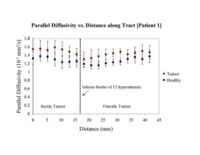

Clustered fibers in the region of the corticospinal tract have been used to identify regions of interest for slice-by-slice measurements of its diffusion properties in normals and tumor subjects. A pilot study (with Monica Lemmond at Harvard Medical School and Stephen Whalen and Alexandra Golby at Brigham and Women's Hospital/HMS) has demonstrated changes in tumor-affected tracts (relative to the contralateral side) beyond the apparent tumor border. A larger study is currently underway.

Monica E. Lemmond, Lauren J. O'Donnell, Stephen Whalen, and Alexandra J. Golby Characterizing Diffusion Along White Matter Tracts Affected by Primary Brain Tumors Abstract accepted to HBM 2007